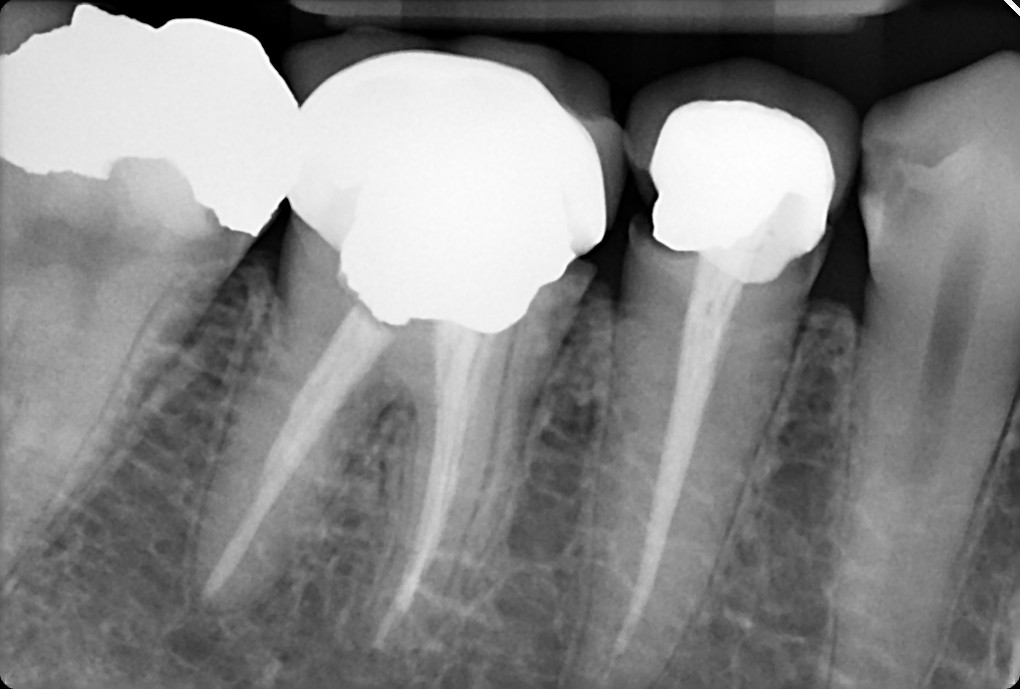

11. On which surface a recurrent caries can be detected?

12 / 35

12. On which surface a recurrent caries can be detected?

Mesial 4.7 is normal proximal caries not recurrent, distal 4.6 is recurrent , mesial 4.6 and distal 4.5 are open margin